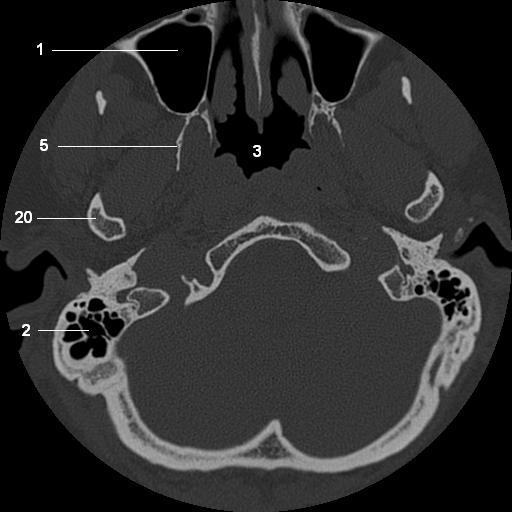

1.   maxillary sinus

2.   mastoid air cells

3.   nasopharynx

5.   lateral pterygoid plate

20. mandible